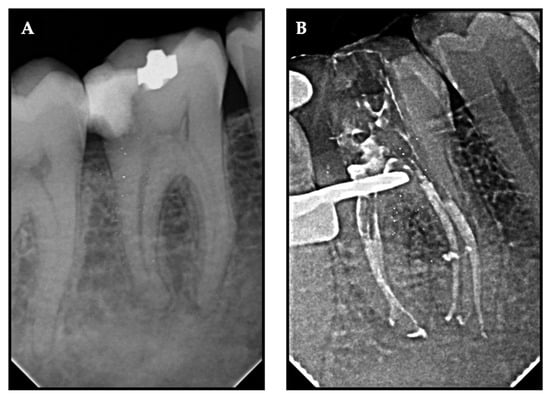

Figure 3. Representative radiovisiographs (RVGs) of (A) pre-operative and (B) post-obturation X-ray exhibiting sealer extrusion.

To fill all of the imperfections in the root canal system, endodontic sealers should have the ideal flow properties. Insufficient flowability may limit appropriate filling, while increased flow rate may raise the possibility of extrusion. Filling material that flows past the apex may cause more pain or may contact significant anatomical landmarks [32]. For the SAF and manual groups were not associated with sealer extrusion whereas in the XPS group exhibited sealer extrusion in 9 cases (Figure 3). However, no flare up was reported by any patient, which is in accordance with Graunaite et al. [33]. One could infer that sealers’ cytotoxic effects might affect how painful treatment feels. However, our results revealed that pain persisted with or without sealer extrusion. Consequently, our clinical findings did not support any possible negative consequences discovered in vitro that were reported by Rodriguez-Lozano et al. recently [34].